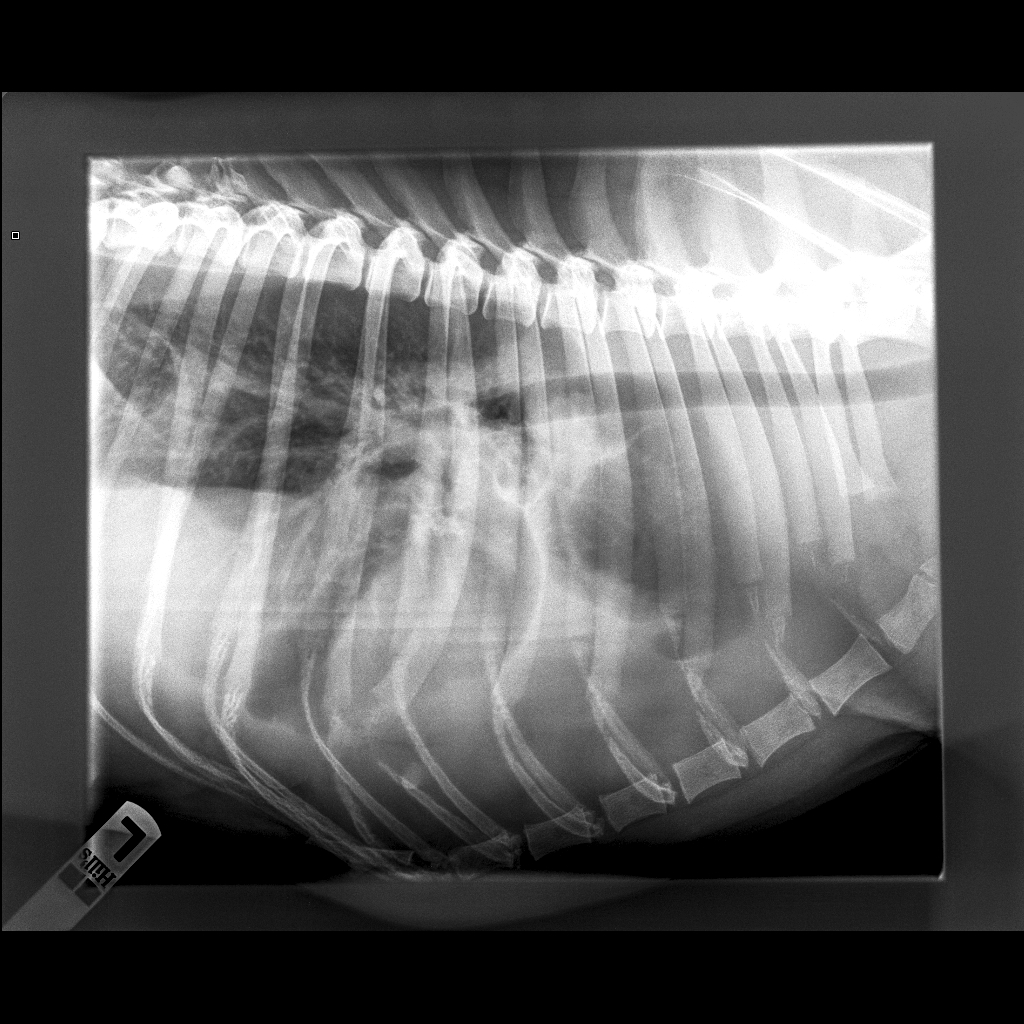

Røntgenbillede optaget ved Tamayas indlæggelse med symptomet dyspnø. Massive udfyldninger i hele thorax komprimerer lungerne.

Peter Maasbøl Skov husker de indledende undersøgelser af hunden. - På røntgenbillederne af thorax kunne man se massive væskeudfyldninger, der komprimerede lungerne og var årsag til dyspnøen. Vi tappede 1,4 liter væske ud, forklarer han og gennemgår billederne på sin skærm.